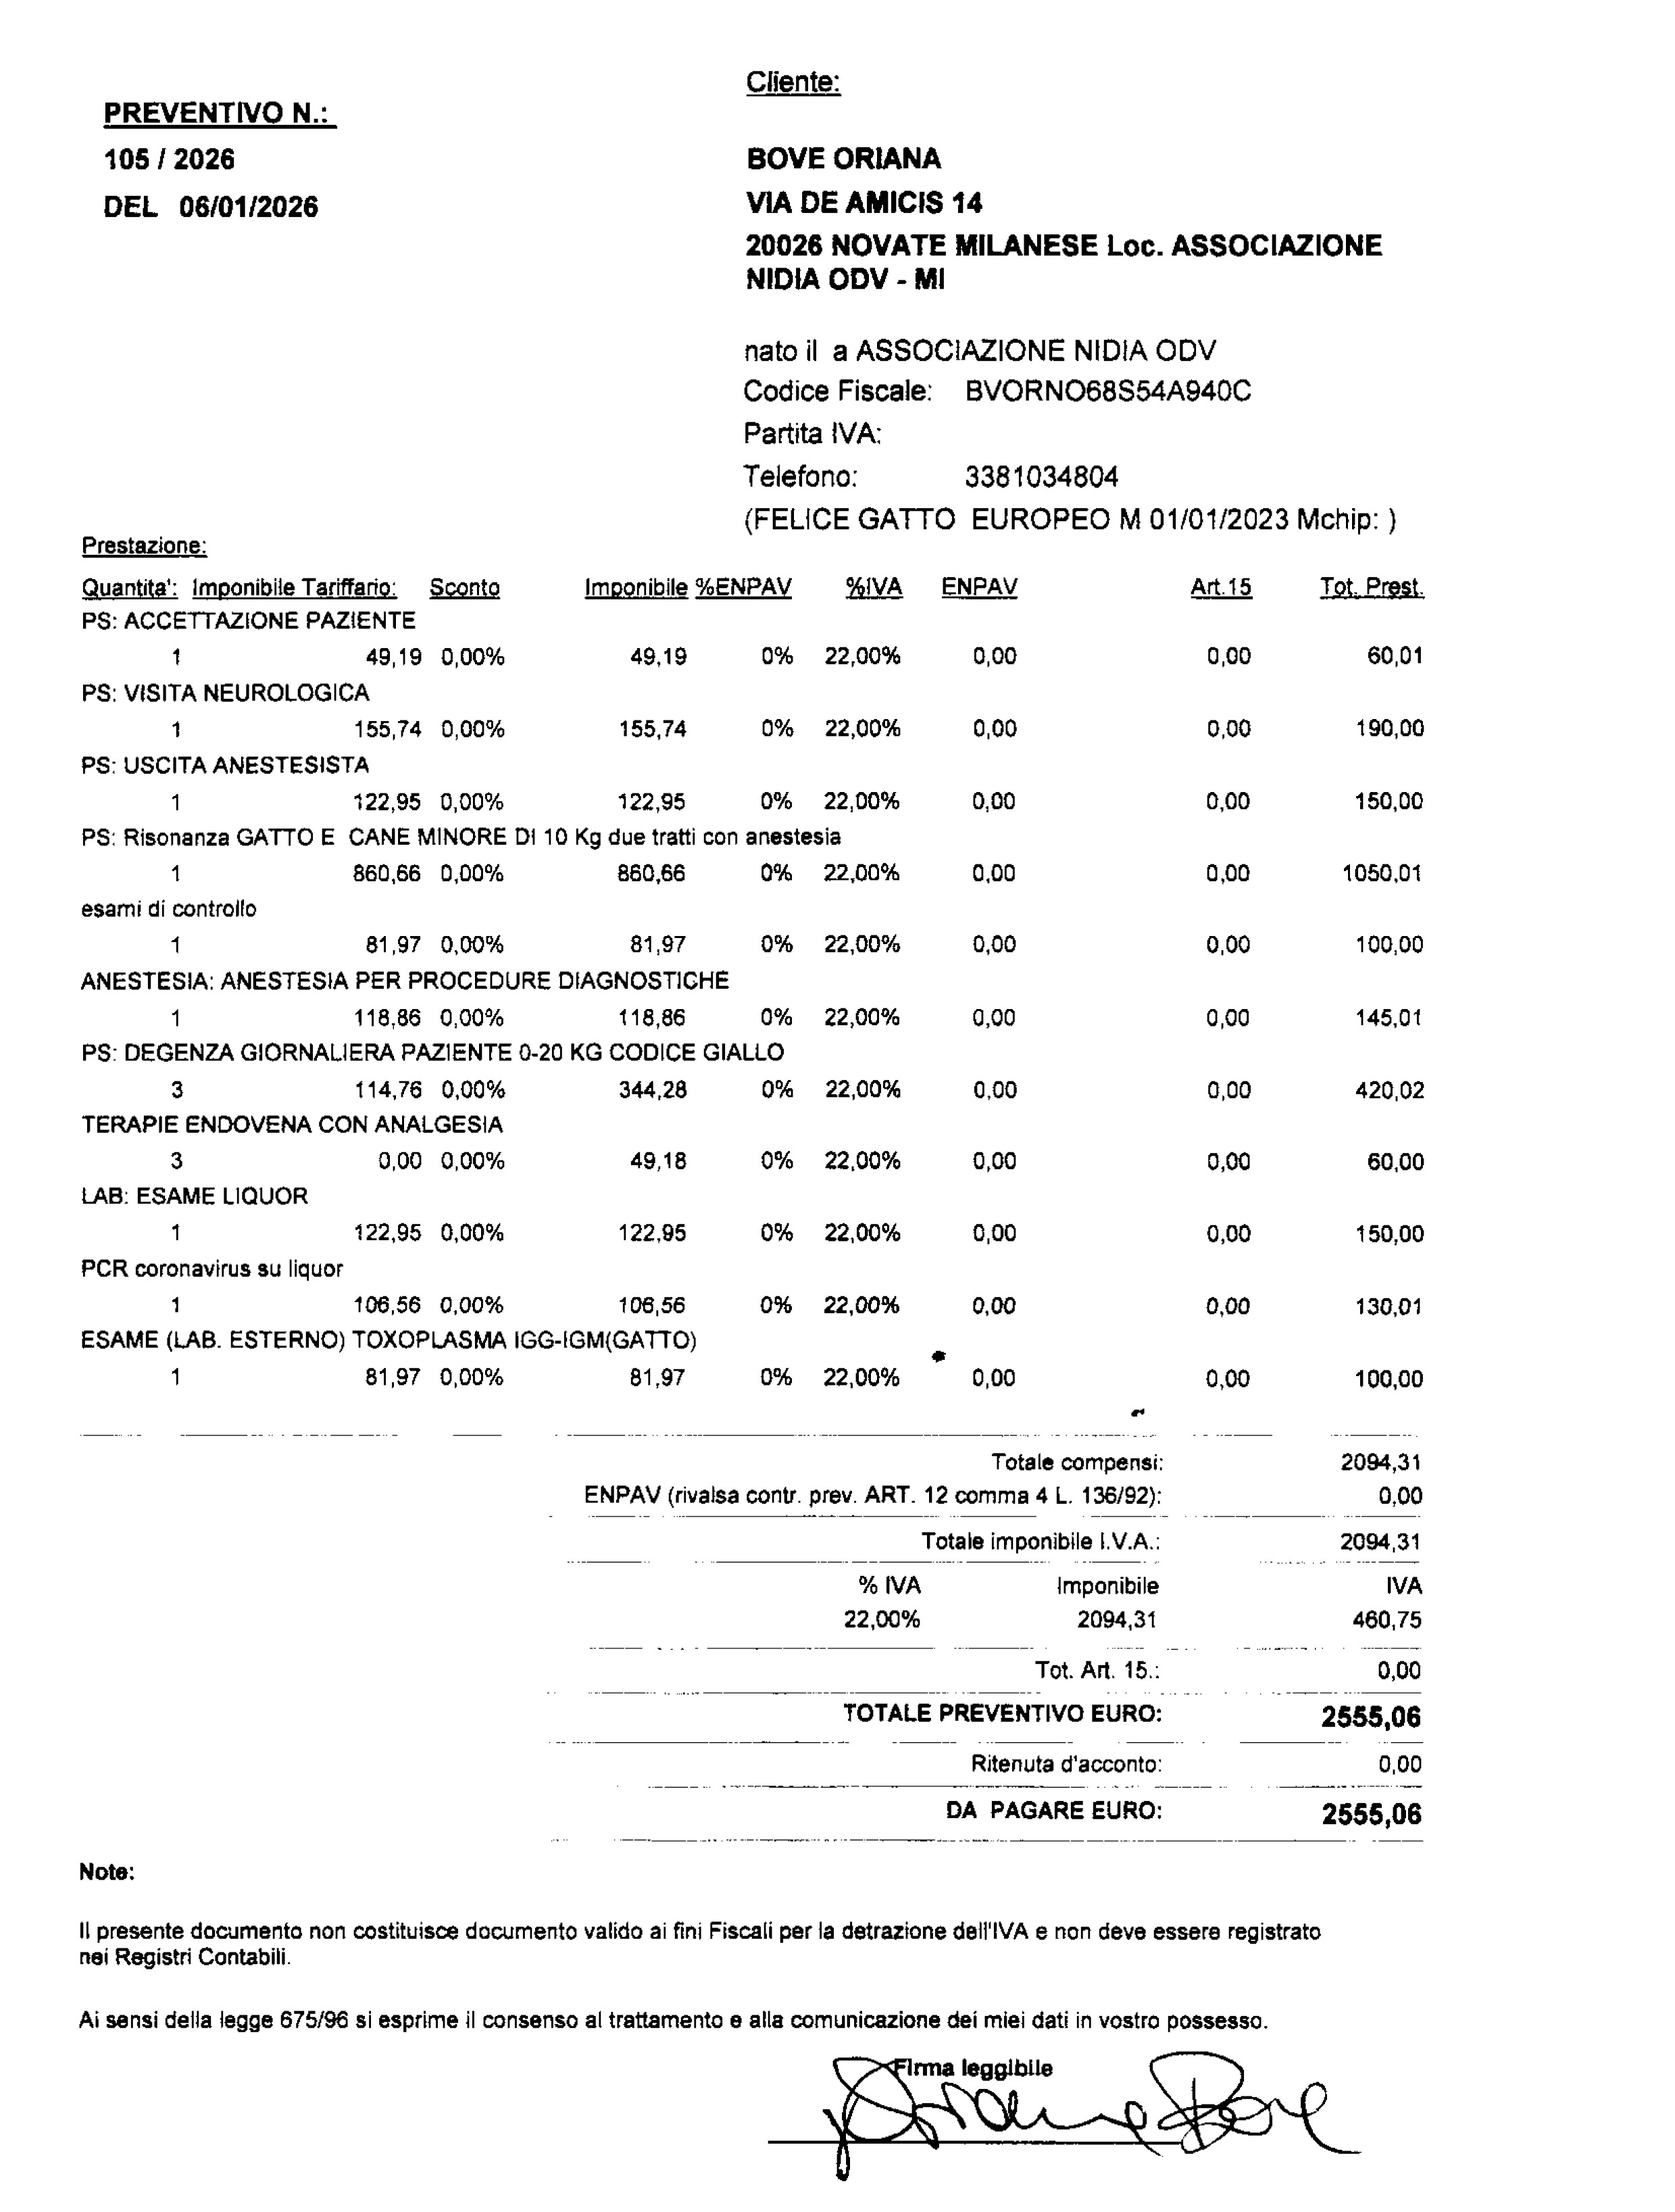

Lo trasferiamo in un’altra clinica per una Risonanza Magnetica e ulteriori indagini.

Purtroppo, l’intervento per rimuovere il proiettile non può ancora essere eseguito:

la FIP deve prima essere stabilizzata, perché un’operazione in queste condizioni sarebbe troppo rischiosa.

Il proiettile resta lì, vicino alla spina dorsale, come un ricordo crudele di ciò che ha subito… in attesa del momento in cui potremo finalmente toglierglielo.

E questo significa che ci saranno ulteriori spese importanti nei prossimi mesi:

le fiale per la cura della FIP, che non sono incluse nel preventivo iniziale,

e l’intervento chirurgico per rimuovere il proiettile, che potrà essere programmato solo quando Felice sarà abbastanza forte.

Per sostenerlo abbiamo aperto una raccolta fondi su GoFundMe, perché le cure sono tante e Felice ha bisogno dell’aiuto di tutti.